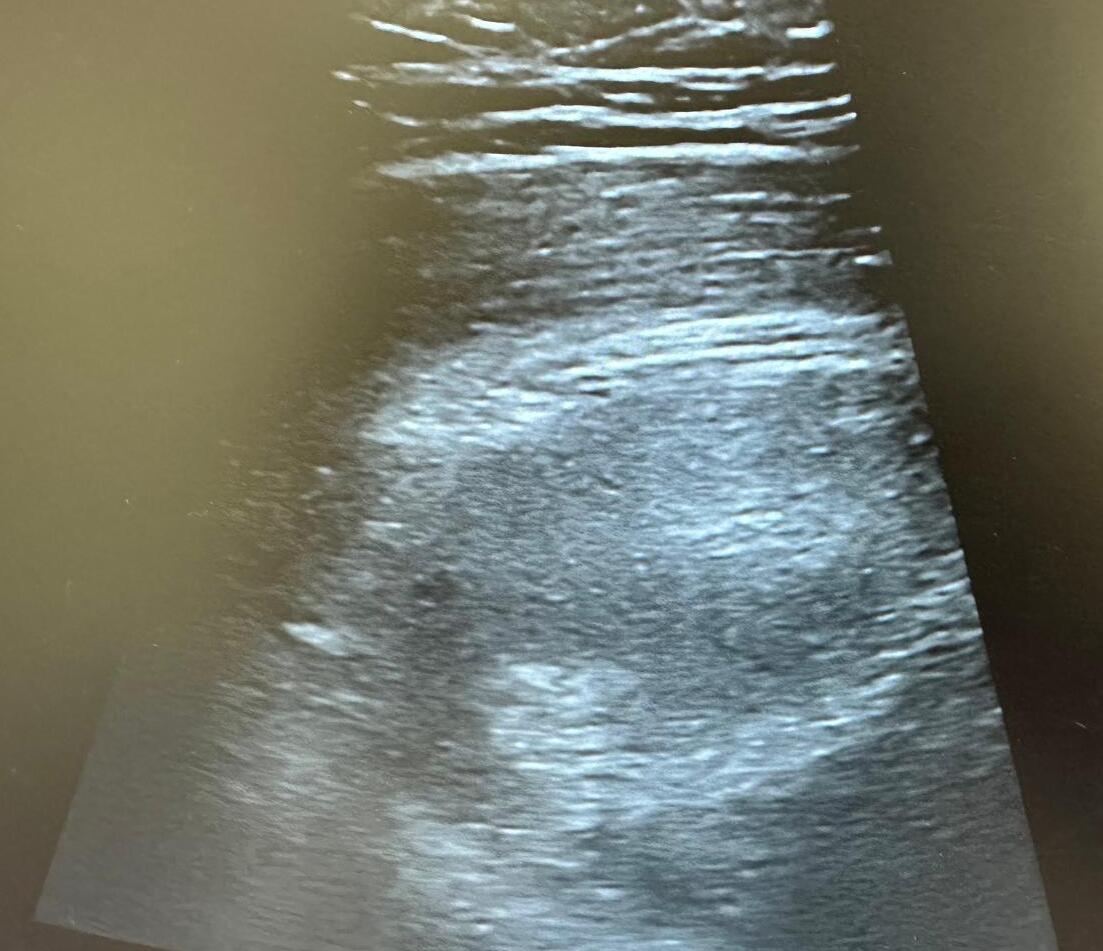

A nivel ecográfico se visualiza imagen profunda, heterogénea, de márgenes poco definidos, sin captación Doppler, más profunda que el margen del glúteo medio.